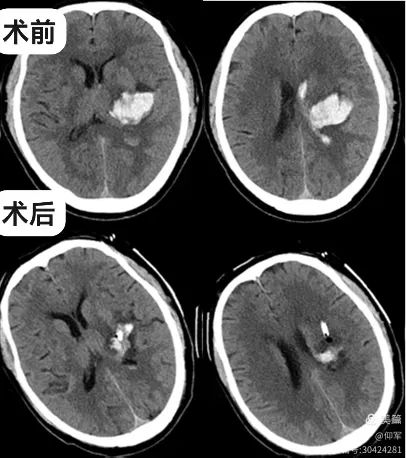

入我院后,查体:嗜睡,言语含糊,右侧肢体肌力1级。复查头颅CT示出血较前增加且破入脑室,约25ml。

诊断:左侧丘脑出血破入脑室,高血压3级(很高危)。患者病情危重,出血增加,出血量尚未达到开颅标准,保守治疗风险大,考虑丘脑出血位置较深,故给予立体定向下脑内血肿穿刺外引流术。

术后第三天复查头颅CT可见血肿大部分已引流,引流管位置精准,手术效果良好。